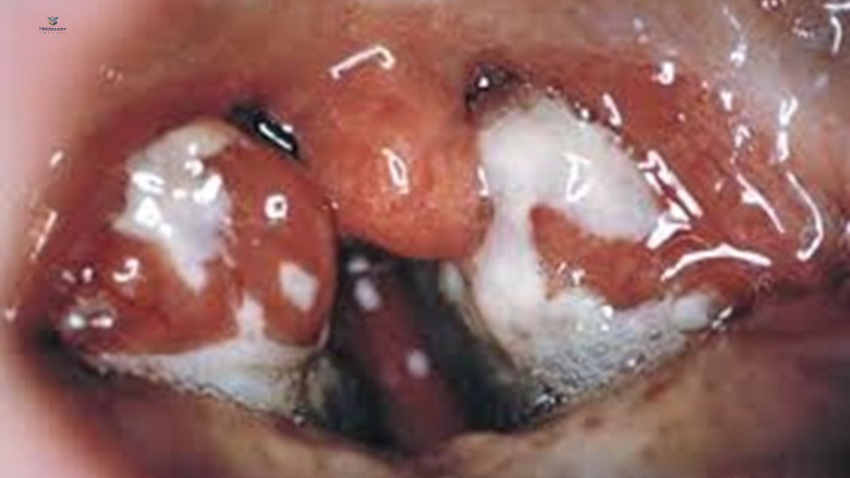

بیشتر بیماران (>۹۰٪) دچار لکوسیتوز ۱۰٬۰۰۰ تا ۲۰٬۰۰۰ سلول/µL هستند که حداقل دوسوم آن لنفوسیت است.

لنفوسیتهای آتیپیک معمولاً ۲۰–۴۰٪ کل لکوسیتها را تشکیل میدهند.

این سلولهای آتیپیک در واقع لنفوسیتهای T بالغ هستند که بهصورت آنتیژنی فعال شدهاند.

ظاهر میکروسکوپی لنفوسیت آتیپیک نسبت به لنفوسیت معمولی:

درشتتر (بزرگتر از نظر اندازه کلی)

هسته بزرگتر با جایگاه اگزانتریک (خارج از مرکز)

هسته فرورفته/شیاردار و تاخورده (indented & folded)

نسبت هسته به سیتوپلاسم کمتر (nuclear-to-cytoplasm ratio پایینتر)

نکته: لنفوسیتوز آتیپیک در عفونتهای دیگر هم دیده میشود، اما بیشترین شدت لنفوسیتهای آتیپیک بهطور کلاسیک در EBV دیده میشود.